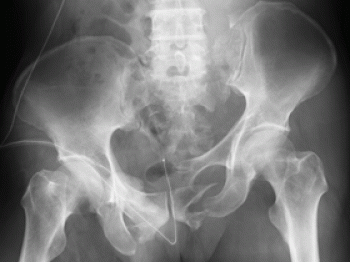

骨盤は、寛骨(腸骨、坐骨、恥骨)+ 仙骨 + 尾骨 で構成しています。

そして、骨盤は、仙腸関節と恥骨結合部を有した環になっています。

骨盤骨折の分類

骨盤の分類は、大きく2つに別れていて、骨盤の環が保たれているか、離断したものか

①骨盤骨単独骨折

腸骨、坐骨、恥骨に骨折があっても、環の連続性が保たれているもの

②骨盤骨環骨折

前者に比べて骨盤骨が形成する環の連続性が骨折によって離断されたもの